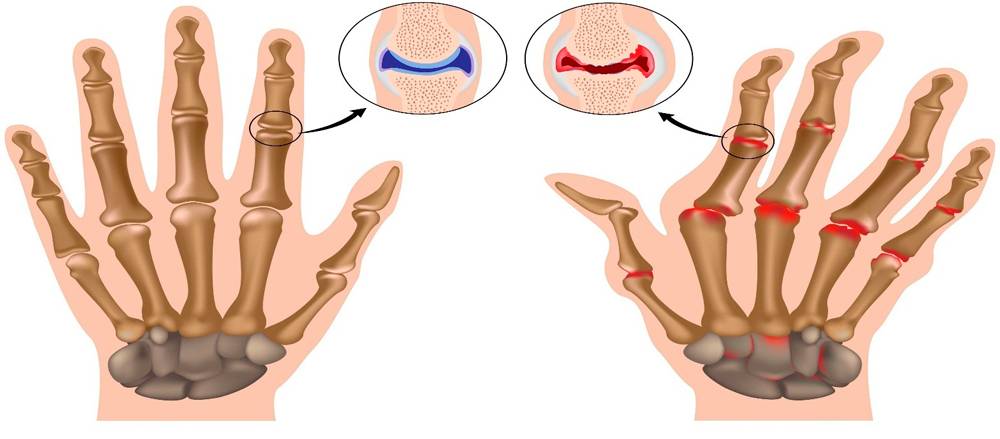

Под воздействием различных внешних и внутренних причин в организме происходят изменения: снижается объем синовиальной жидкости, питающей хрящ. Покрывающий головки суставных поверхностей хрящ постепенно истончается, теряет эластичность, растрескивается и разрушается. Это приводит к разрастанию костной и соединительной ткани, изменению формы и снижению функции мелких суставчиков. Процесс сопровождается постепенно нарастающим болевым синдромом.

Артрит. Воспалительный процесс в суставе приводит к расслоению, истончению и трещинам хрящевой ткани. Если заболевание не лечить, изменения со временем затрагивают и кость: на ней появляются наросты, уплотнения и шипы. Далее происходит деформация кости, из-за чего возникают отеки и сильные боли даже в состоянии покоя.

- Артрит (воспаление одного или нескольких суставов). Изменения в хрящевой ткани при артритах проявляется трещинами, расслоением, истончением, что приводит к появлению скрипения при движениях в суставе. Кроме того, хруст и треск связаны с изменениями в костной ткани — появлением уплотнений, шипов, наростов.